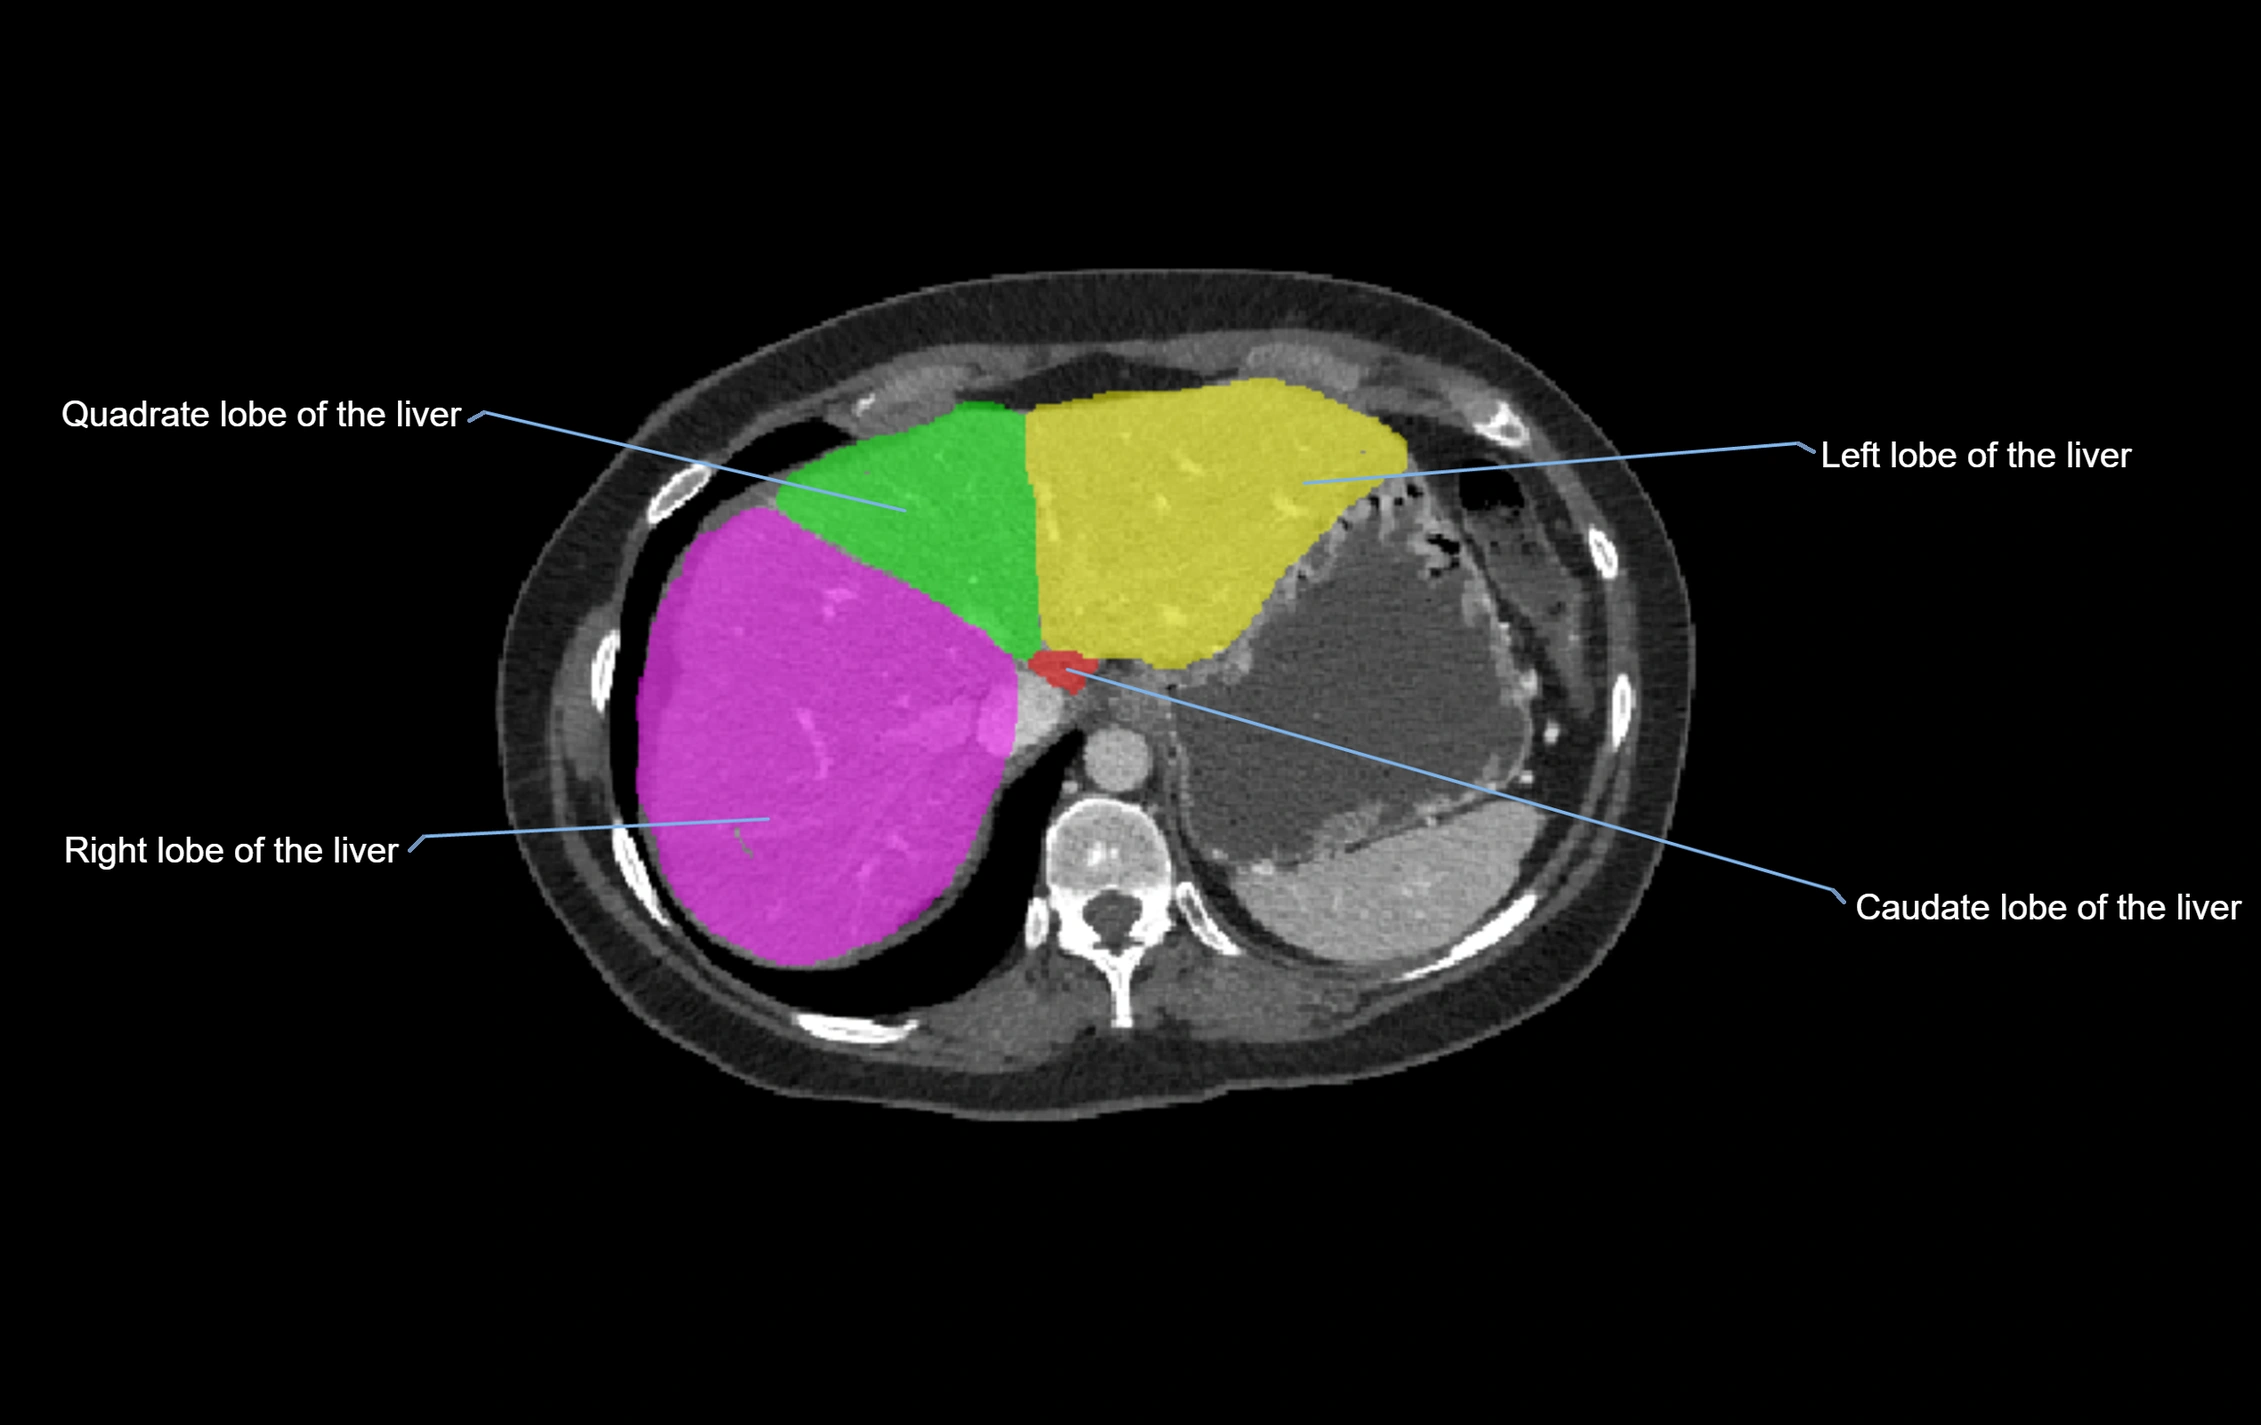

CT Image

image